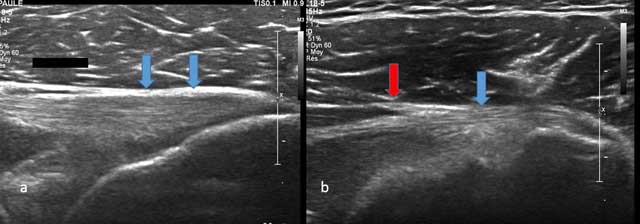

The tendon is examined with the arm in abduction and external rotation (similar to the infraspinatus tendon examination). Analysis is performed arms along the body in internal rotation or hand onto the contralateral shoulder (Figure 1). Sagittal cross sections are the most informative and the tendon appears to be short, hyper echoic and fibrillar.

Figure 1

Axial view of Teres Minor with tendon (blue arrow) and musculotendinous junction (red arrow).